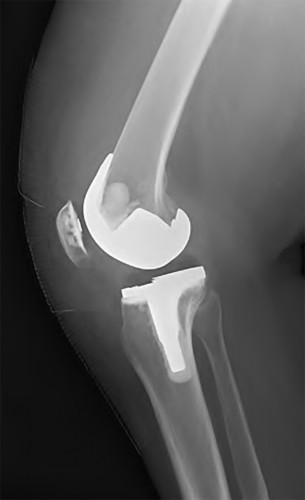

A 65-year-old woman with painful knee arthritis and the deformity seen in Figure A, is scheduled to undergo a total knee arthroplasty. All the following are risk factors for a post-operative peroneal palsy EXCEPT:

Figure A demonstrates and AP radiograph of the knee showing end-stage arthritis with severe lateral compartment narrowing.

The clinical presentation is consistent with end-stage arthritis in a valgus knee. All of the factors listed are risk factors for peroneal nerve palsy EXCEPT female gender, which is not a risk factor.

Peroneal nerve palsy is a potential serious complication of TKA in patients with a pre-operative valgus knee deformity. Peroneal nerve palsy is likely caused by lengthening of the lateral aspect of the knee and subsequent traction on the peroneal nerve. It is generally recommended that patients be evaluated

carefully for symptoms postoperatively. If peroneal nerve palsy symptoms are discovered, the knee should be flexed to relax the tension that is effectively being placed on the nerve. If peri-operative nerve exploration or decompression is undertaken, the posterior border of the biceps-femoris tendon is the proper site of identification.

Idusuyi et al. published a retrospective review of 32 postoperative peroneal nerve palsies in thirty patients in which they identified possible risk factors. Prior proximal tibial osteotomy, lumbar laminectomy (thought to be a “double-crush” phenomenon), and preoperative valgus alignment of 12 degrees or more were all identified as risk factors. Other concerns included epidural anesthesia for postop pain control, preoperative flexion contractures and tourniquette time greater than 120 minutes also increased concern.

Favorito et al reviewed valgus total knee arthroplasty and reported that the most common complications of patients with a valgus deformity include: tibiofemoral instability (2% to 70%), recurrent valgus deformity (4% to 38%), postoperative motion deficits requiring manipulation (1% to 20%), wound problems (4% to 13%), patellar stress fracture or osteonecrosis (1% to 12%), patellar tracking problems (2% to 10%), and peroneal nerve palsy (3% to 4%).